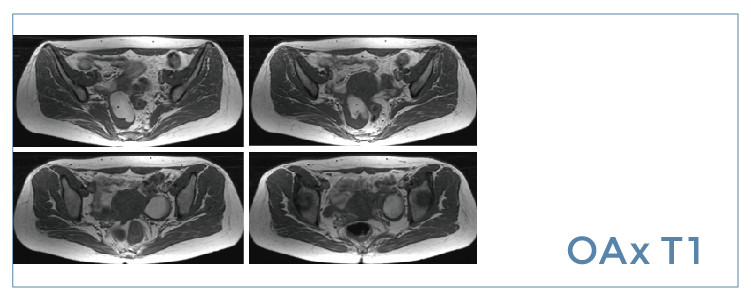

【朗润影像档案】20190705磁共振影像病例结果讨论